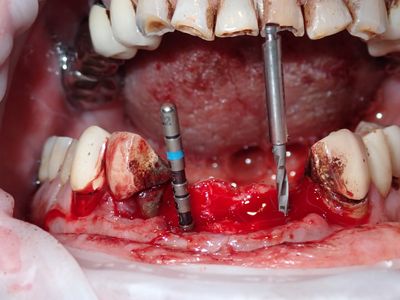

relatively straight forward implant placement in the upper anteriors, densah drills used after 2.2mm twist drill. 21 loss of stablity, spinning, when trying to place deeper, removed implant, deepened osteotomy, implant replaced with good stability.